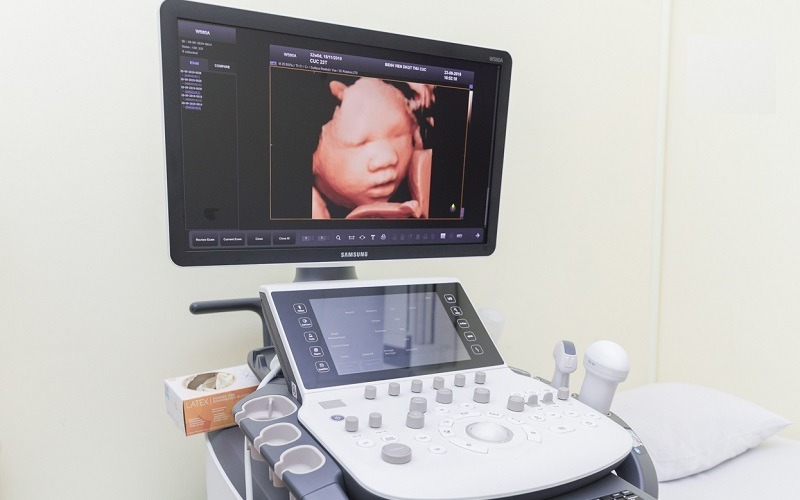

Siêu âm 4D và 5D đều sử dụng sóng siêu âm tần số thấp, không gây đau, không xâm lấn và được đánh giá là an toàn cho mẹ bầu và thai nhi. Các nghiên cứu y khoa cho thấy siêu âm không gây ảnh hưởng đến sự phát triển của thai nếu thực hiện đúng chỉ định và số lần hợp lý. Tuy nhiên, mẹ bầu không nên lạm dụng siêu âm chỉ để “ngắm bé” quá nhiều lần, mà cần thực hiện theo hướng dẫn của bác sĩ. Để đảm bảo an toàn tối đa, mẹ nên siêu âm tại cơ sở uy tín với đội ngũ bác sĩ giàu kinh nghiệm và thiết bị hiện đại.